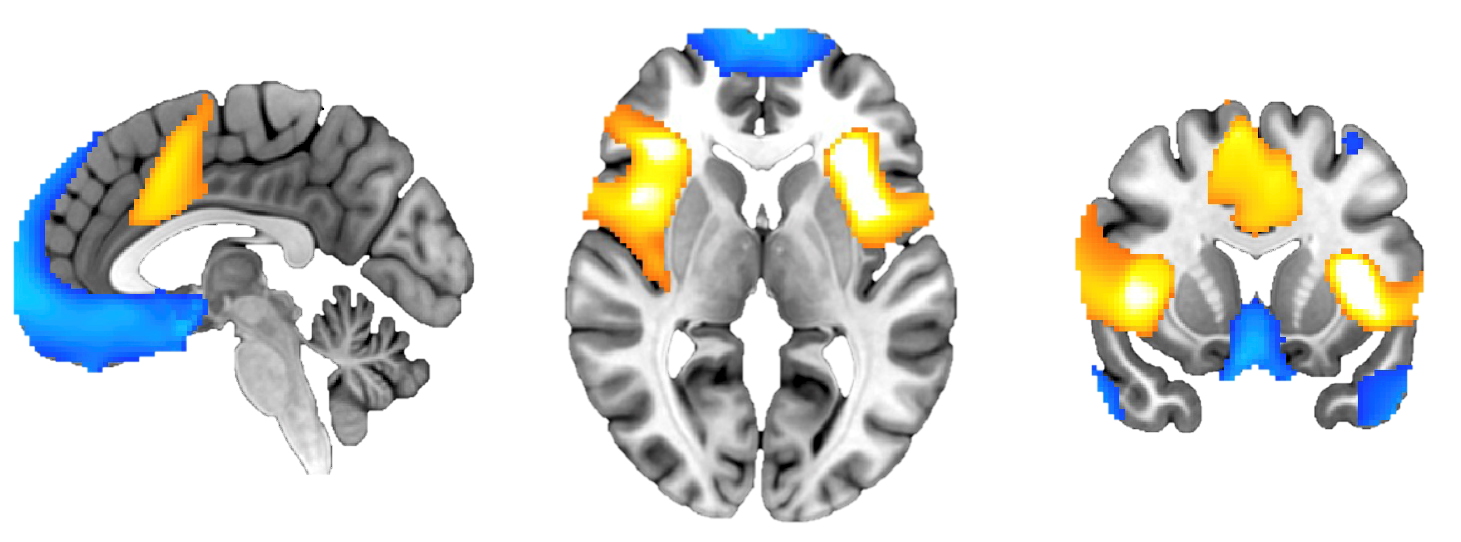

Tutkimuksessa tunnistettiin riippuvuussairauksien kannalta olennaiset aivoverkostot. Tulosten perusteella riippuvuuden hoidossa saattaa olla hyödyllistä vähentää lämpimillä väreillä merkittyjen alueiden toimintaa ja vahvistaa kylmillä väreillä merkittyjen alueiden toimintaa. Kuvan alkuperäinen versio on julkaistu tutkimusartikkelissa Nature Medicine -lehdessä.